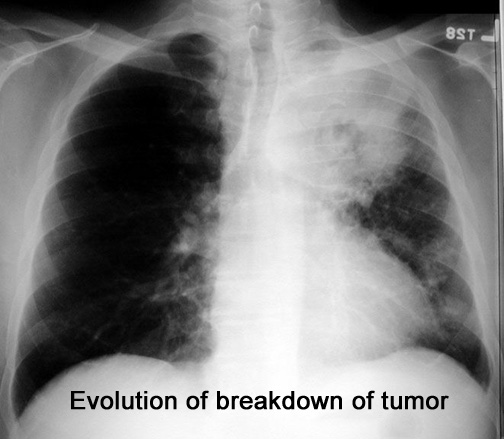

Case 12 Labeled Image

Labeled Image

Follow the progression of break down of tumor. What are stalactites and stalagmites?

Observe the progression of breakdown of tumor explaining the radiological findings.